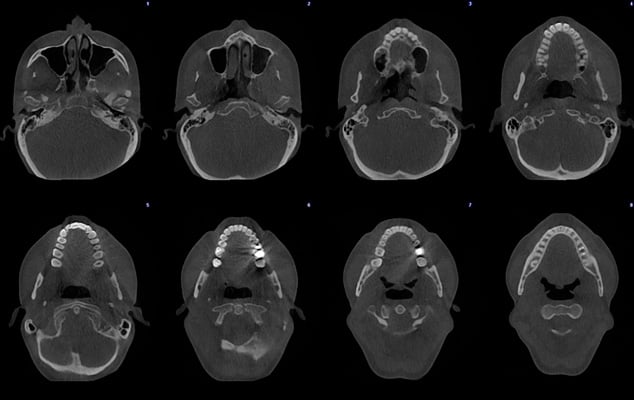

Ultra low dose image - Orthodontic case

Planmeca ProMax 3D - FOV Ø 85 x 50 mm. - Voxel size 400 µm - Effective patient dose 7.9 µSv

Planmeca ProMax 3D - FOV Ø 85 x 50 mm. - Voxel size 400 µm - Effective patient dose 4.0 µSv